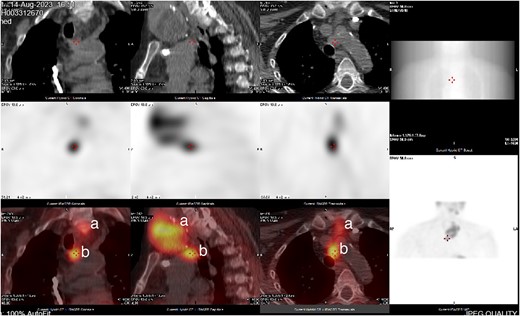

She was subsequently referred to our service for further surgical evaluation. At the time of referral, she was asymptomatic. Initial blood tests showed an elevated PTH of 1256 pg/ml (range 15–65 pg/ml), reduced adjusted calcium of 2.05 mmol/l (range 2.21–2.52 mmol/l), normal free T4 at 19.9 μg/dl (range 12–22 μg/dl), and a reduced TSH <0.01 mU/l (range 0.27–4.20 mU/l), along with a raised phosphate of 2.32 mmol/l (range 0.81–1.45 mmol/l). A CT neck showed a large left thyroid mass with a differential diagnosis of metastatic lymphadenopathy versus a parathyroid adenoma. She underwent an ultrasound and fine needle aspiration of the thyroid mass, which revealed a Thy3A lesion with no evidence of malignancy. Following further multidisciplinary team (MDT) discussion, an immunostain for PTH was performed on the EBUS TBNA, which revealed that the oncocytic cells were positive for PTH (see Figs 1 and 2). This was confirmed by a sestamibi scan, which confirmed a sestamibi-avid nodule (see Fig. 3).

CT neck and sestamibi scan of coronal, sagittal, and axial view of superior mediastinum with mediastinal ectopic parathyroid nodule. (a) Thy3A thyroid nodule; (b) mediastinal parathyroid nodule.

It was decided that the Thy 3A nodule did not warrant surgery as it was completely benign. In addition, there was a biopsy-proven mediastinal parathyroid nodule and given that this patient had significant co-morbidities including a recent myocardial infarction and was asymptomatic of her HPT, the consensus was that surveillance was considered the safest option. On follow-up, her PTH was 1100 IU, and calcium was 2.0 mmol/l. She was followed up in our clinic for surveillance thereafter.